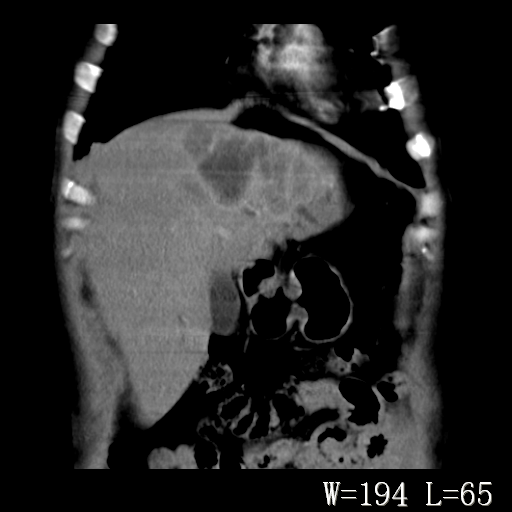

标题: CT27340:肝脏病变?

男,45岁,发热、乏力半月,午后为主。

对比剂快进快出,首先考虑肝左叶巨块型肝癌。

其次,感染性病变,如肝脓疡不排除。

蜂巢,肝脓肿

蜂巢状,支持!肝脓肿的诊断。